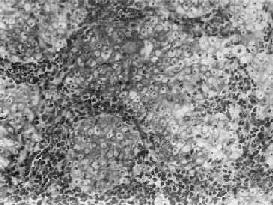

(3)泡状核细胞癌:癌巢不规则,境界不甚明显,癌细胞胞浆丰富,境界不清晰,往往呈合体状聚集成堆。核大呈空泡状,圆形或卵圆形,有1~2个肥大的核仁,核分裂像并不多见(图9-6)。癌细胞间常可见淋巴细胞浸润。电镜下,可观察到紧挨淋巴细胞的癌细胞胞膜和胞质有破坏现象,这可能是淋巴细胞对癌细胞免疫攻击的结果。

图9-6 鼻咽泡状核细胞癌

癌细胞境界不清,呈合体状,核大圆形,染色质少,呈空泡状,含1~2个肥大的核仁,癌细胞间有淋巴细胞浸润